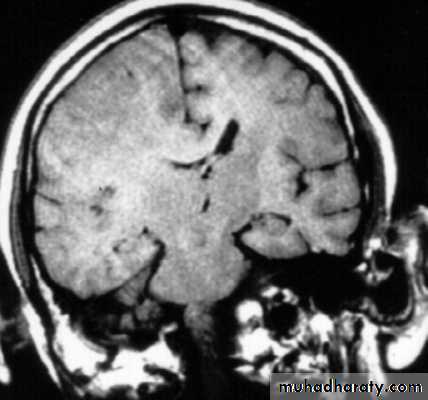

Investigations of Intracranial Hypertension

A. Skull X- RayB. Computed Tomography (CT Scan) of Brain.

C. Magnetic Resonance Imaging (MRI) of Brain

The CT and/or MRI scan will show no cause for the papilloedema and the ventricles will often be smaller than usual.